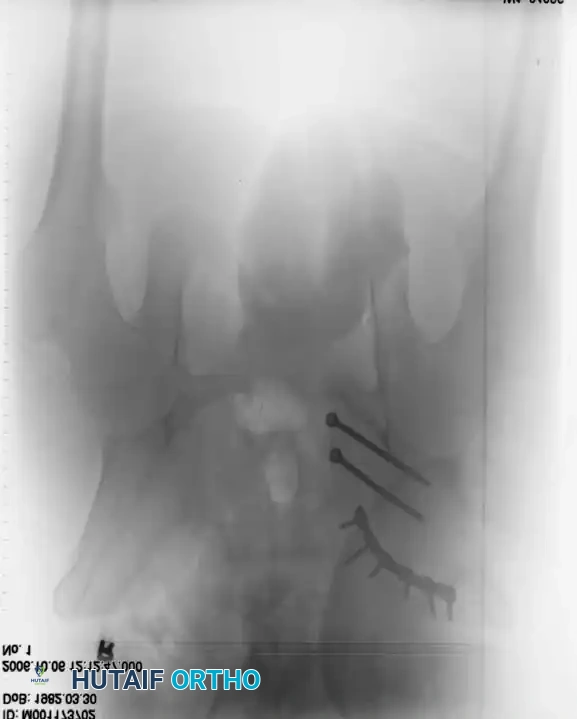

3. Percutaneous Sacroiliac (SI) Screws (Posterior Ring)

The gold standard for posterior ring fixation in appropriately selected patients.

* Indications: Sacral fractures, SI joint disruptions, crescent fractures.

* Technique: Performed under strict fluoroscopic guidance (Inlet, Outlet, and Lateral sacral views).

* Trajectory: The guide wire is advanced from the lateral ilium, across the SI joint, into the S1 (or S2) vertebral body.

* Safety Corridors: The surgeon must possess an intimate understanding of sacral dysmorphism. The "safe zone" is bounded by the sacral neural foramina inferiorly, the spinal canal posteriorly, and the sacral ala anteriorly.

Pitfall: Failure to recognize a dysmorphic sacrum (characterized by upper sacral segment elevation, non-recessed alae, and oblique neural foramina) can lead to catastrophic L5 nerve root injury or vascular penetration during SI screw placement.

Image